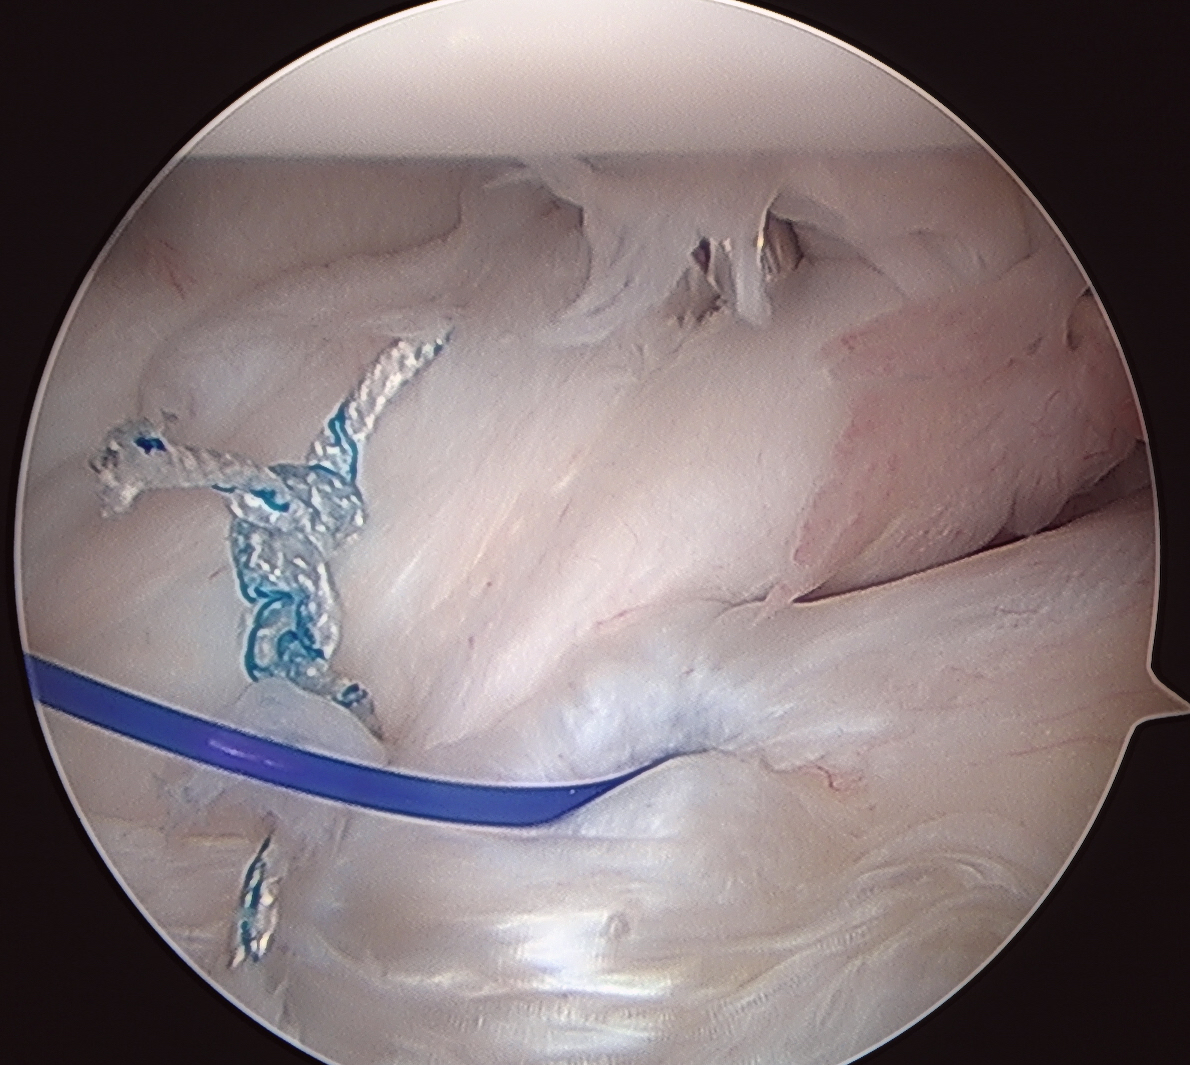

Side to side suture repair +/- HAGL repair

Side to side repair of capsular tear

Intact anterior labrum with capsular tear, axillary nerve seen below capsular tear in axillary recess